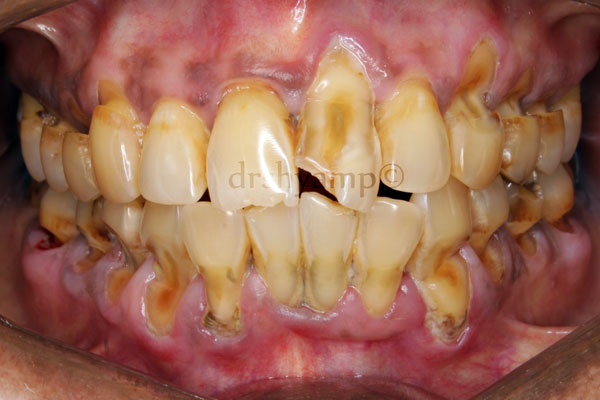

Wasting of the tooth (tooth wear) is defined as any gradual loss of tooth substance characterized by the formation of smooth, polished surfaces, without regard to the possible mechanism of this loss. They have been classified as:

Attrition is occlusal wear resulting from functional contacts with opposing teeth. A certain amount of tooth wear is physiologic, but accelerated wear may occur when abnormal anatomic or unusual functional factors are present. Significant amount of attrition in young adults is unlikely to occur from functional wear and is probably the result of bruxing / clenching / tooth grinding activity.

erosion is a sharply defined, wedge-shaped depression in the cervical area of the facial tooth surface. Erosion generally affects a group of teeth. Suggested causes include decalcification by acidic beverages or citrus fruits and the combined effect of acid salivary secretion and friction

In general, clinical features of gingivitis may be characterized by the presence of any of the following clinical signs: redness and sponginess of the gums, bleeding on provocation, changes in contour, and presence of calculus or plaque with no radiographic evidence of crestal bone loss.